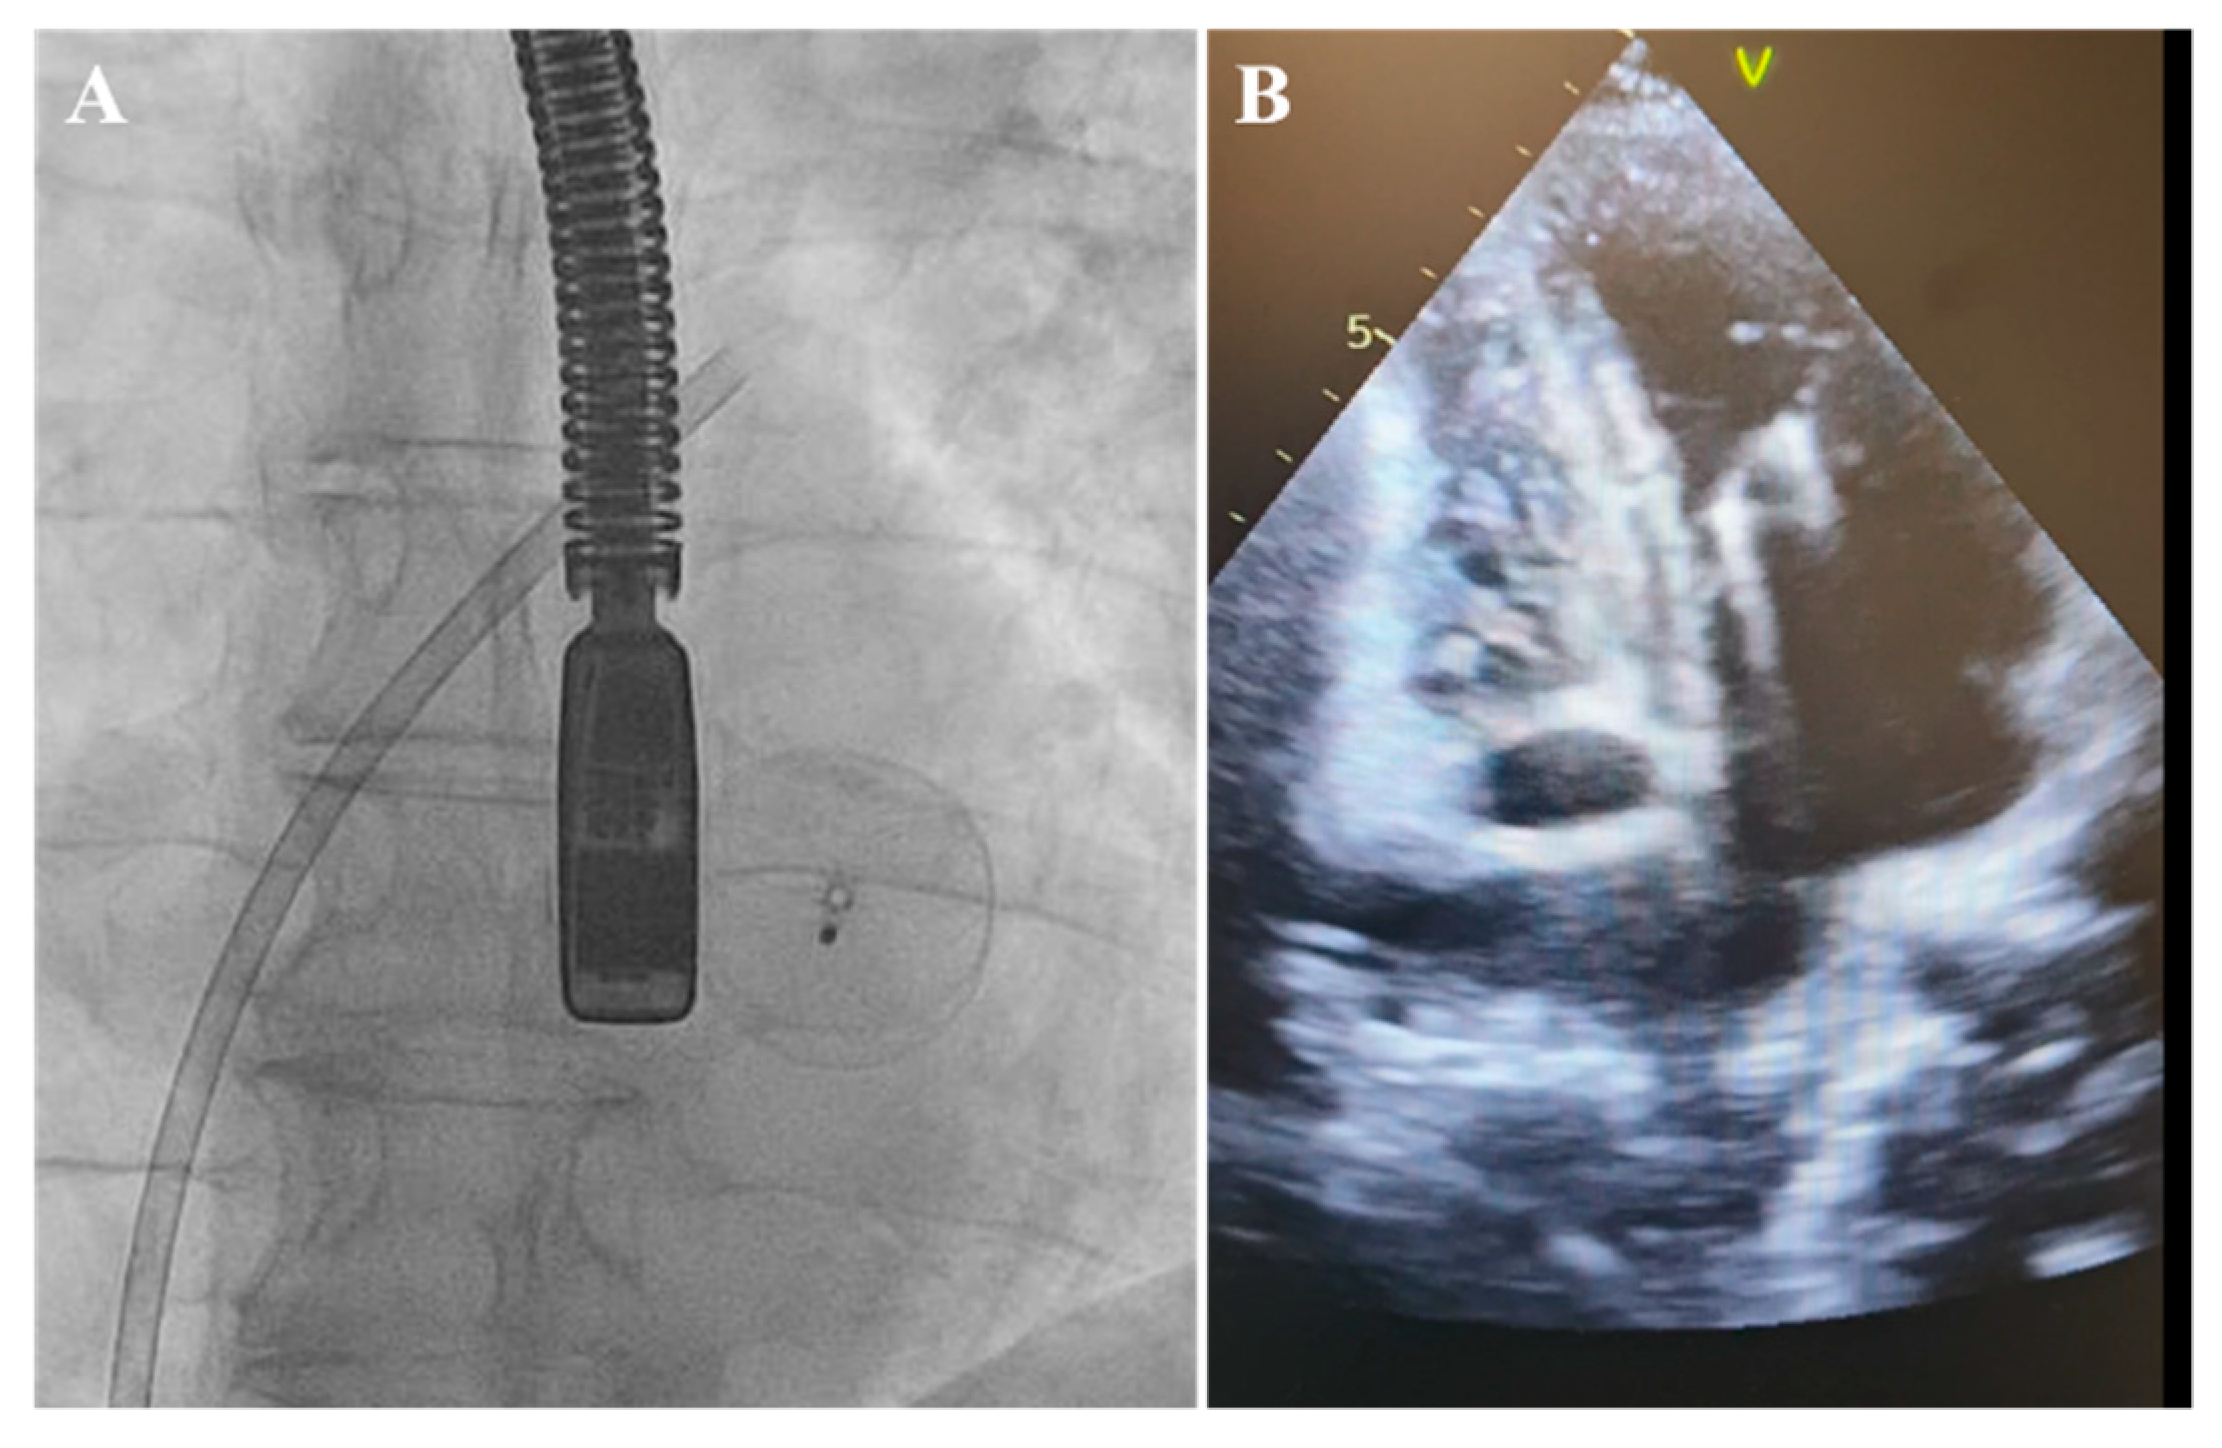

Therefore, in response to the notably aneurysmatic, floppy, and thin interatrial septum, to prevent the unintended slippage of the PFO closure device, we undertook efforts to reposition the occluder to stabilize a large portion of the septum despite recognizing that this might have necessitated the use of a larger device. Following this adjustment, the PFO occluder was unexpectedly and unintentionally detached, without the release of the device safety mechanism. Initially, the position of the PFO occluder was confirmed on the radiogram in the projection of the left atrium (LA) and then in the left ventricle (LV) projection (Figure 3).

Figure 3.

Detached occluder in the projection of the left ventricle. (A) Fluoroscopy. (B) Transthoracic echocardiography.

The attempts to snare it from the LA and LV were unsuccessful. Furthermore, the device promptly migrated to the abdominal aorta, located below the diaphragm at the junction of the truncus coeliacus, which was confirmed via a CT scan (Figure 4).